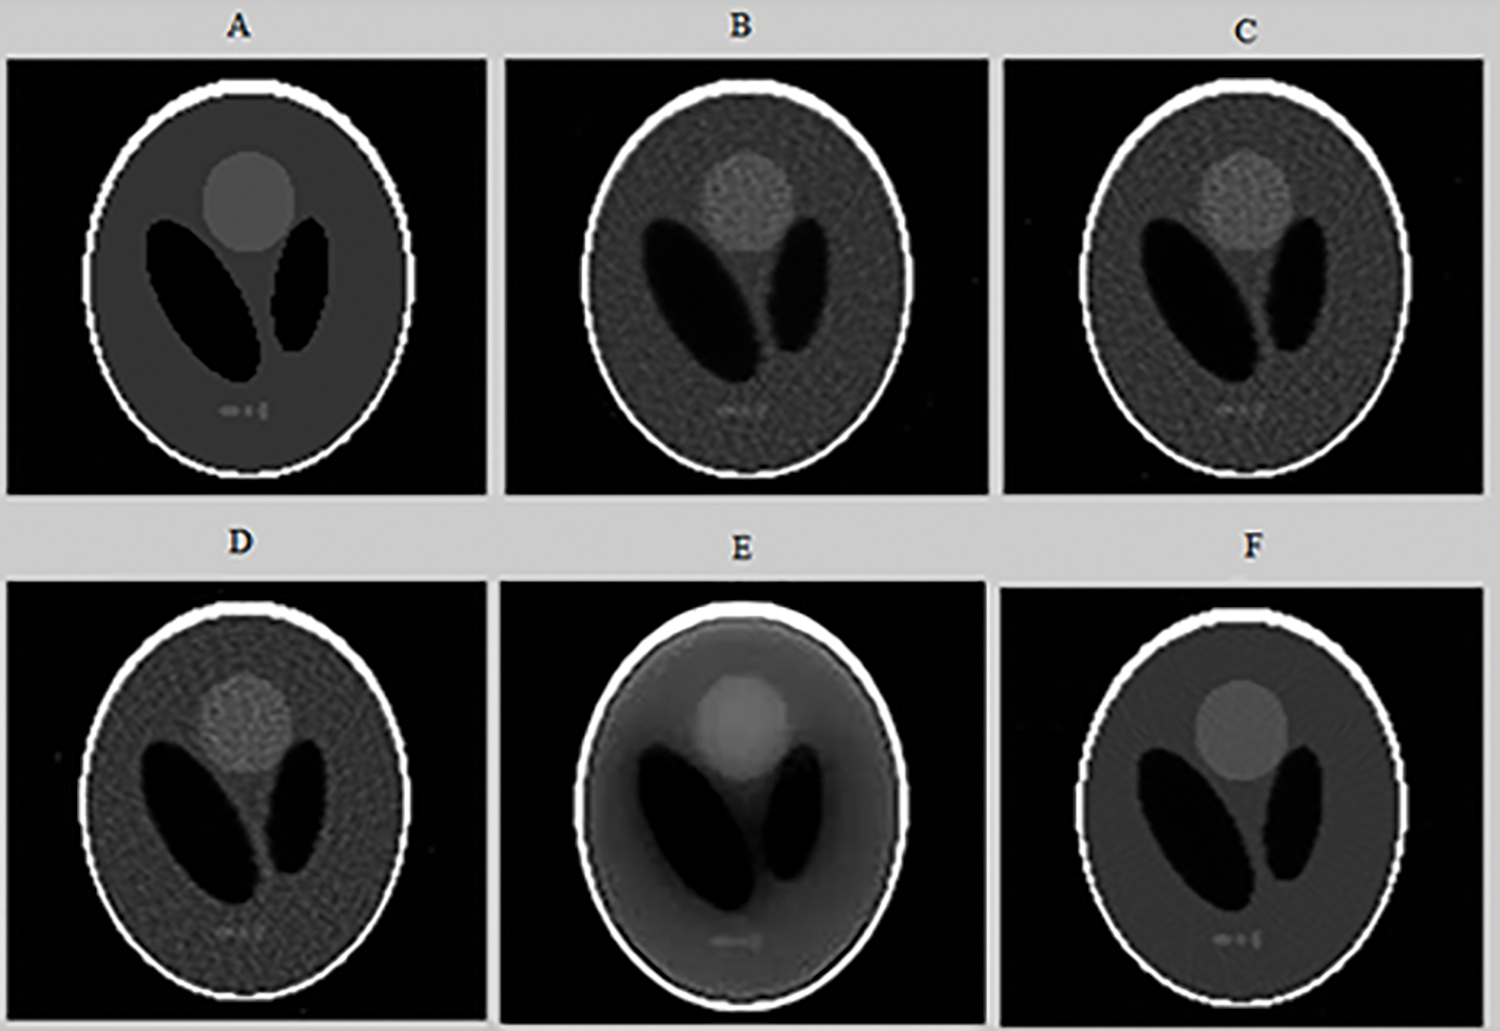

Axial slices reconstructed from a SPECT image of a Jaszczak by various reconstruction methods are shown in Fig. 12.

Figure 12: Axial slices (slice 73) reconstructed from the SPECT image of a Jaszczak phantom. (A) CT image; (B) Slice reconstructed by MLEM with 10 iterations; (C) Slice reconstructed by OSEM with (8 iterations and 4 subsets); (D) Slice reconstructed by OSEM with post-filtering by Metz filter; (E) Slice reconstructed by CNNR and (F) Slice reconstructed by the proposed method

From Fig. 12, it can be seen that the shape of the sphere seems more spherical and the background less uniform in the reconstructed slice with the proposed method. Whereas in the reconstructed slice with the other methods, the shape of the sphere seems slightly smoothed and attenuated, making the extraction and localization of the contours difficult and giving a much noisier image. This result shows the accuracy and efficiency of our proposed method in the reconstruction. It allows better preservation of detail and region boundaries than the other methods.